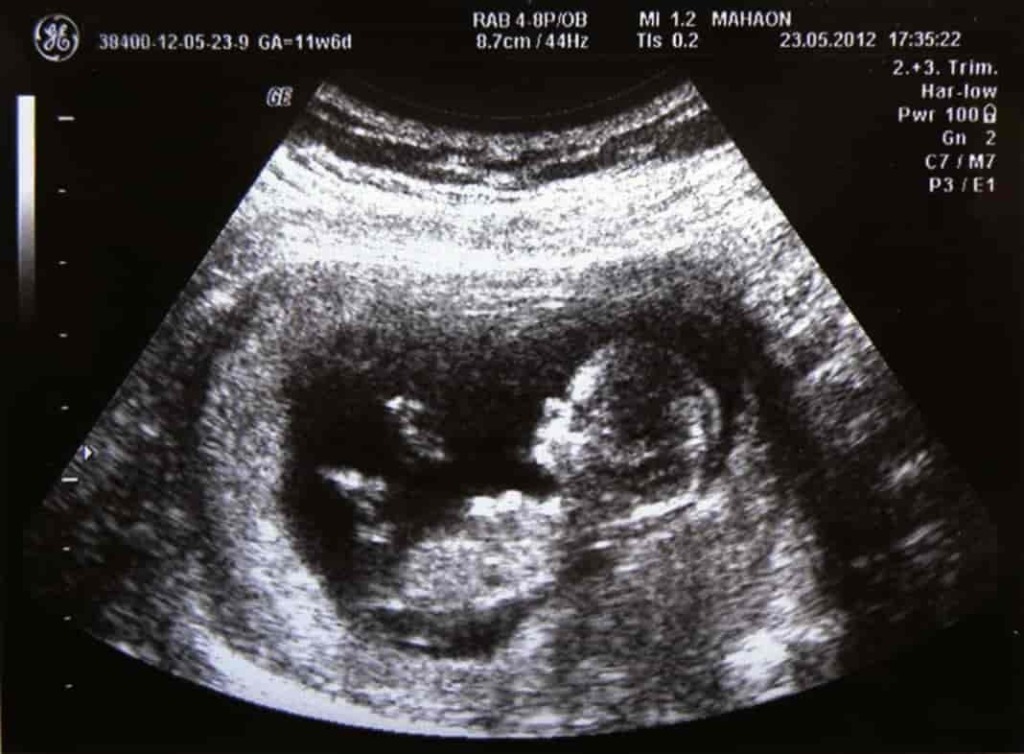

У супругов Морис родился ребенок, больной тяжёлым генетическим заболеванием – спинальной амиотрофией. Забеременев во второй раз, заявительница сделала анализ околоплодных вод, который показал, что дитя, носимое под сердцем, страдает этим же заболеванием. Родиться ему было не суждено, беременность была прервана.

Надежда родить здорового ребенка не покидала супругов, и в следующую беременность госпожа Морис вновь отправилась делать амниоцентез. И тут ее обрадовали, анализ дал отрицательный результат.

Родилась девочка. В какой-то момент родители обнаружили, что она отстаёт в развитии. Вердикт врачей был неутешительным: больна. Больна спинальной амиотрофией, точно так же, как и ее старшая сестра.

Морисы обратились с иском к клинике. И тут выяснилось, что в свое время были перепутаны баночки с образцами околоплодных вод, что и явилось причиной сообщения родителям неверной информации о здоровье ребенка. И, как следствие, появление на свет больного ребенка.